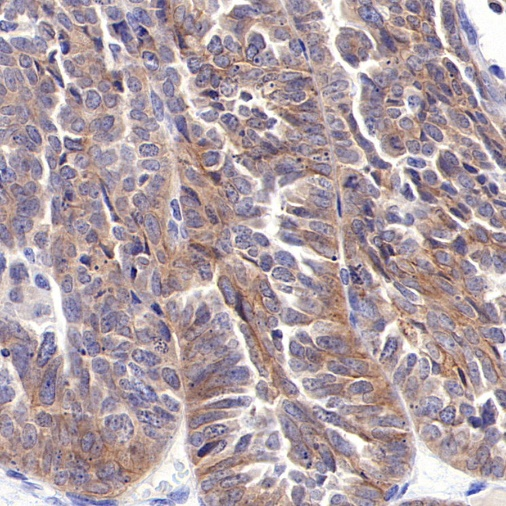

AntBio offers ROR1 recombinant rabbit monoclonal antibodies, which have been validated in human ovarian cancer, gastric cancer, endometrial cancer, and mantle cell lymphoma tissues. These antibodies exhibit higher specificity, sensitivity, and stability, providing more accurate diagnostic results for clinical applications.

Tissue Type: Human Endometrial Cancer